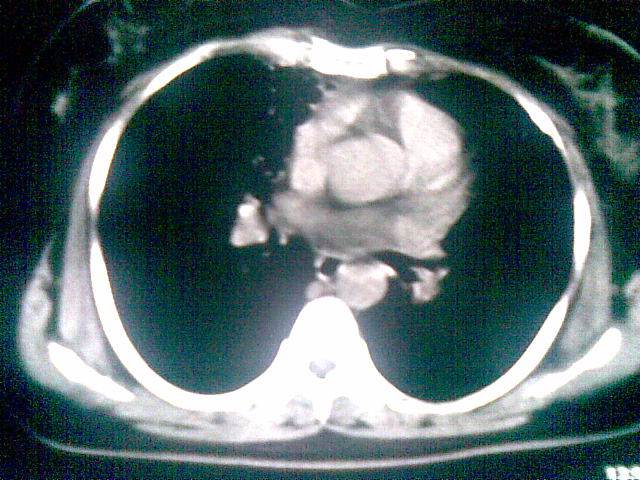

两上肺均见有斑片条结及蜂窝状环状低密度影,以右侧居多,考虑肺结核并支扩可能。

支扩并感染,结核不能排除,建议结合实验室检查或痰检。